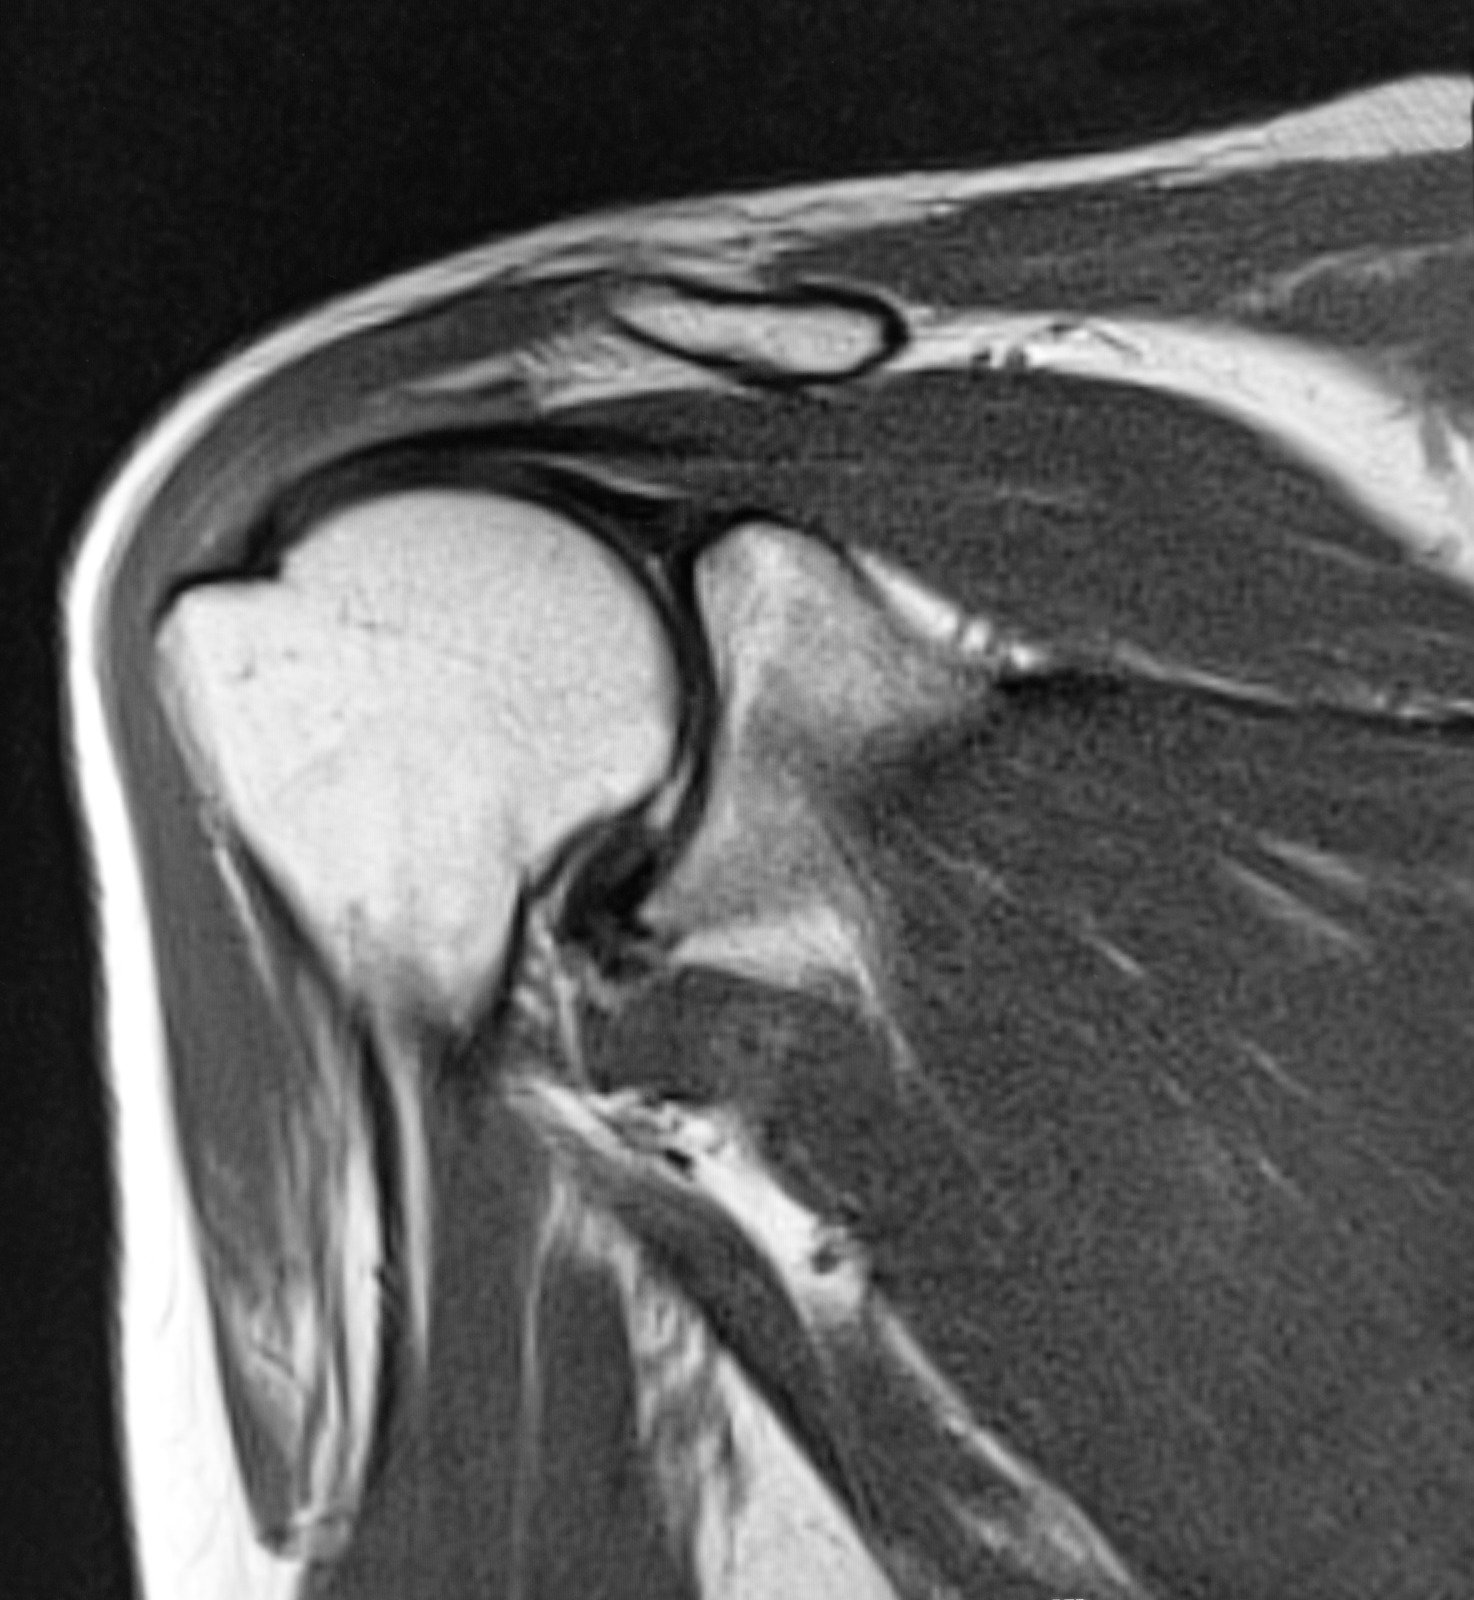

MRI: 회전근개 파열 및 연부 조직 손상 진단

MRI(자기공명영상)는 어깨의 연부 조직(힘줄, 인대, 근육 등)을 상세히 관찰할 수 있는 고해상도 영상 검사 방법입니다.

특히 회전근개 파열과 같은 어깨 연부 조직 손상의 정확한 진단과 평가에 매우 효과적입니다.

1) 회전근개 파열

회전근개: 어깨를 감싸고 있는 네 개의 근육과 힘줄(극상근, 극하근, 견갑하근, 소원근)로 구성.

MRI로 확인할 수 있는 내용:

파열의 유형: 부분 파열, 전층 파열.

파열 크기와 위치: 힘줄의 손상 정도와 주변 조직 상태 평가.